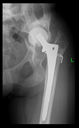

The radiological examination allowed us to verify the close bone-to-implant contact and the unchanged position of the implant during follow-up.

In all the cases operated with the above-described targeting procedure, the stems of the cups remained between the cortical bone surfaces without perforation of the linea terminalis, as shown by postoperative radiographs. There were no complicated surgical situations. In 16 cases, the wound healings were uneventful, and the hips were able to bear weight again after postoperative rehabilitation.